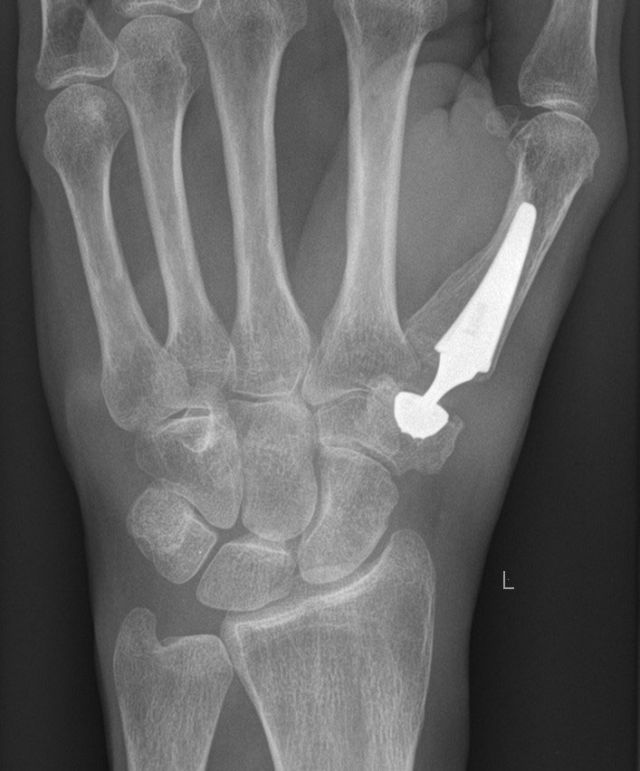

Postoperatives Röntgen: Implantierte Daumensattelgelenksprothese

Seit Anfang 2019 führen wir auch wieder die Implatantation von Kunstgelenken (Gelenkprothesen) in das Daumensattelgelenk durch. Es gibt Sattelgelenksprothesen bereits seit über 3 Jahrzehnten, allerdings zeigten diese keine guten Langzeitergebnisse. Seit kurzem sind jetzt Prothesen auf dem Markt, welche die konstruktiven Probleme der "alten" Systeme beseitigt haben und deutlich bessere Langzeitergebnisse versprechen.

Im Vergleich zur RSA hat die Sattelgelenksprothese den Vorteil, dass das grosse Vieleckbein erhalten bleibt und bei einem eventuellen Versagen der Prothese die RSA weiterhin möglich wäre.

Die Prothese hat auch den Vorteil einer kürzeren Nachbehandlungszeit von durchschnittlich 8 Wochen, allerdings ist der technische Aufwand der Operation deutlich höher als bei der RSA.